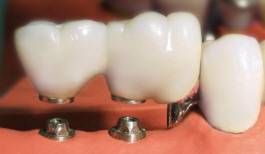

Die Kombinationsprothese:

Die Kombinationsprothese wird eingesetzt, wenn noch ein Restzahnbestand von eigenen Zähnen vorhanden ist. Bei dieser Prothesenart handelt es sich um einen Zahnersatz, der aus einem fest zementierten (Kronen oder Brücken) und einem herausnehmbaren Teil besteht. Um einen besonders guten Halt zu gewährleisten, werden an den Kronen oder Brücken, sowie an der Prothese, Haltelemente angebracht. Dies kann in Form von Stegen, Geschieben oder Teleskopen geschehen. Um einen guten ästhetischen Eindruck zu erhalten, werden die Halteelemente des herausnehmbaren Zahnersatzes verdeckt. (Von außen nicht erkennbar!)

Kombinierter Zahnersatz bietet einen hohen Tragekomfort sowie einen hohen ästhetischen Stellenwert.

Teleskopprothes